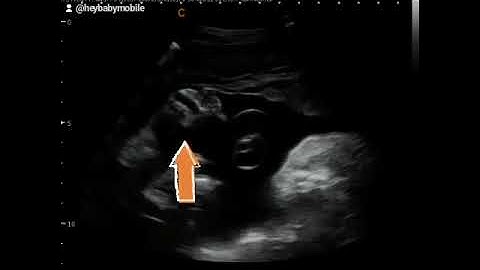

How to acquire 3D/4D images